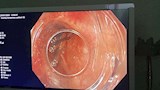

نجحت وحدة المناظير بكلية الطب جامعة حلوان في إجراء أول عملية من نوعها باستخدام منظار الموجات فوق الصوتية لتشخيص واستئصال ورم بالمريء في جلسة واحدة، دون الحاجة إلى إجراء فتحات جراحية، بمستشفى بدر الجامعي.

وتمت العملية في غضون 30 دقيقة باستخدام تقنية مناظير الفراغ الثالث؛ حيث تم تحديد نوع الورم ومكانه وحجمه ومنشئه، عبر منظار الموجات فوق الصوتية، ثم استئصاله مباشرة في نفس الجلسة. وتميزت العملية بتوفير الوقت على المريضة وتجنيبها مخاطر التخدير المتكرر؛ حيث تم خروجها من المستشفى خلال 24 ساعة في حالة صحية ممتازة دون أي مضاعفات.

وأجريت العملية تحت إشراف الدكتور شريف البحيري، مدرس الباطنة العامة بكلية الطب واستشاري المناظير التداخلية ومناظير الفراغ الثالث، والذي تلقى تدريبًا متخصصًا على هذه التقنية المتقدمة في جامعة كاتب أتاتورك بتركيا خلال مهمة علمية من جامعة حلوان.